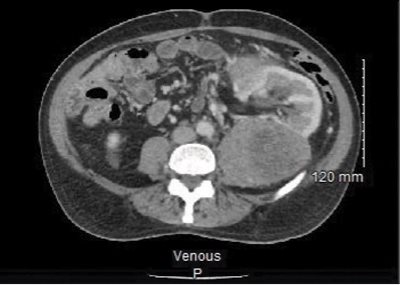

The CT scan impression is as follows: “Huge heterogeneous vascular left-sided retroperitoneal mass displacing adjacent structures and likely renal in origin. Findings most likely represent a renal cell carcinoma.”

The mass is noted to be at least 25 cm in diameter per the radiologist’s interpretation (see Fig. 1), and the left kidney and other local structures are noted to be anteriorly displaced (see Fig. 2).

Fig. 1. CT abdomen with contrast. “Huge” heterogeneous mass of the left abdomen (estimated 25 cm at largest diameter). Left kidney unable to be visualized in this view.